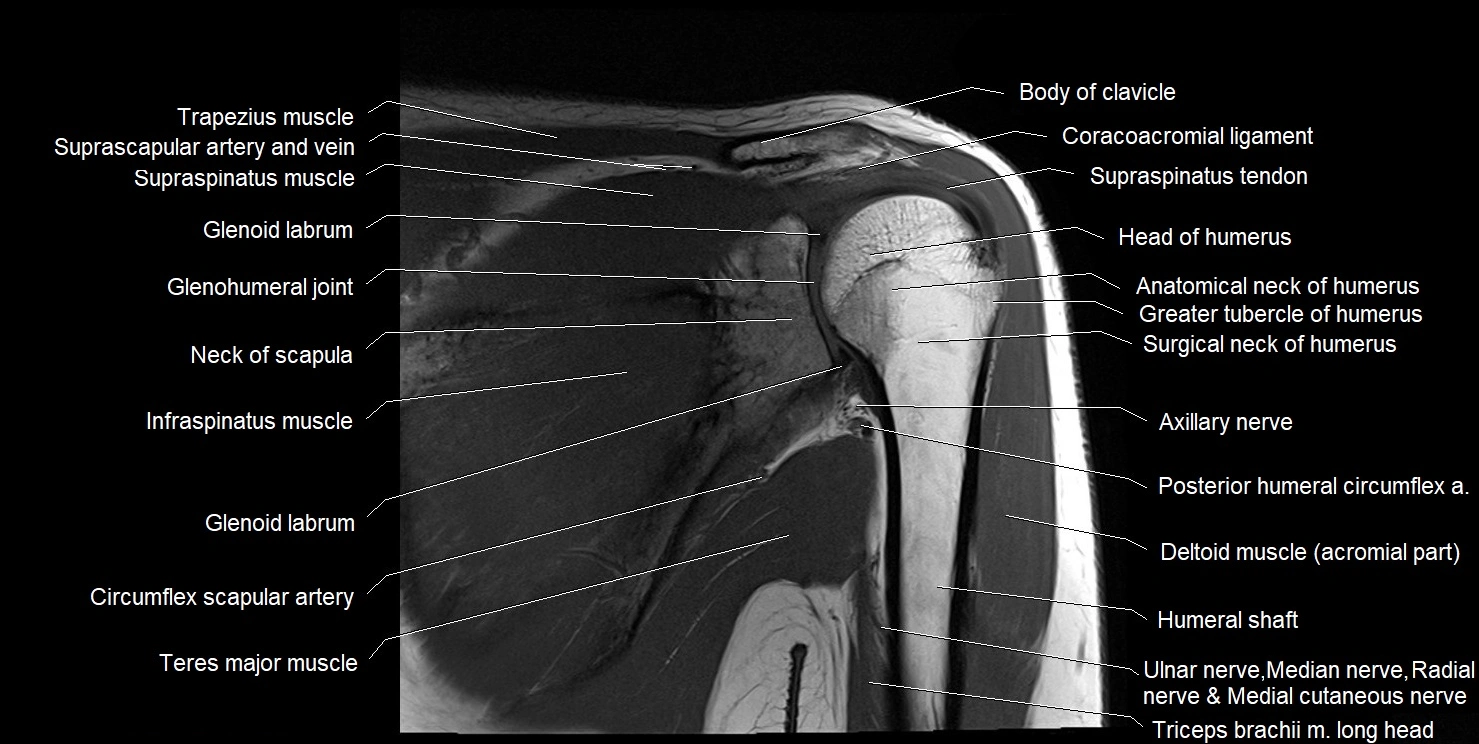

MRI images

image